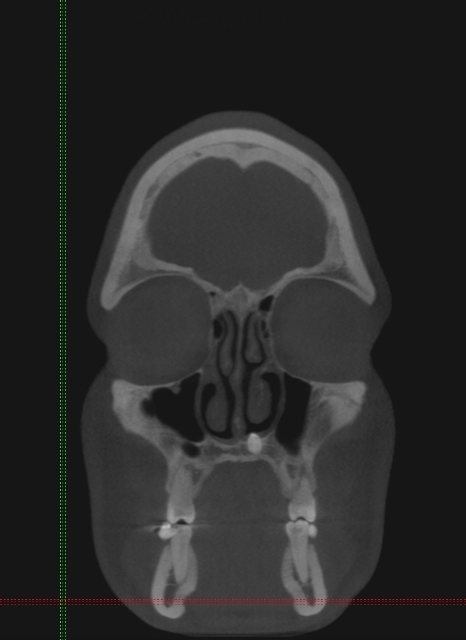

Za razliko od običajnih CT-naprav, kjer rentgenski snop prodira skozi tkivo v ravninah in slika nastane z obdelavo vseh »rezin«, ki so različno narazen (običajno 1 do 3 mm), pri CT-napravah s stožčastim snopom detektorji sprejemajo stožčast snop – podatki dajo sliko prostornine in ne samo ravnine. Naprave so precej manjše, pacientu ni treba ležati, odmerek sevanja, ki ga prejme pacient, je okrog 50-krat manjši, kot pri običajnih CT preiskavah, slika trdih tkiv (torej kosti in zob) pa je neprimerno ostrejša (slike 2, 3, 4).

Slike 2, 3, 4: Posnetki CT-ja s stožčastim snopom. Položaj nadštevilčnega zoba je jasno prikazan v vseh treh ravninah, lepo se vidi, da zob s krono sega v nosno votlino. Zob je mogoče natančno izmeriti.